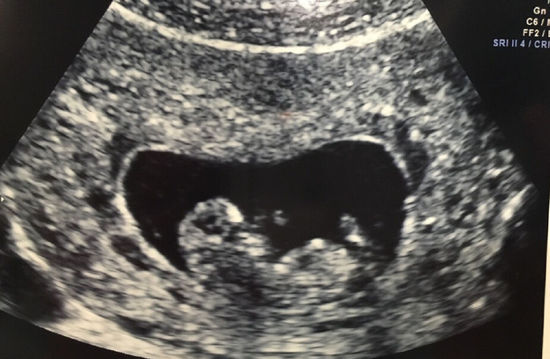

陶昕然宣布怀孕晒B超照 孩子小名叫何陶(图)

陶昕然晒B超照

网易娱乐3月18日报道 今日,陶昕然在微博晒出一张自己B超照,宣布怀孕,她欣喜说道:“大家好,我的小名儿叫何陶,今天是爸爸妈妈的结婚纪念日,我祝爸爸妈妈永远幸福恩爱,百年好合 以后我就可以在这儿和大家聊天儿了是吧,哇咔咔,好开心,么么哒(注:我不叫 核桃 哦 因为妈妈说 她不希望我做一个表皮坚硬内心却脆弱的人,她希望我做一个表皮柔软内心却坚定的人)”。网友纷纷送上祝福:“安小主终于可以有自己的孩子啦,哈哈哈哈哈”“恭喜娘娘有喜了!”“恭喜安小主!”